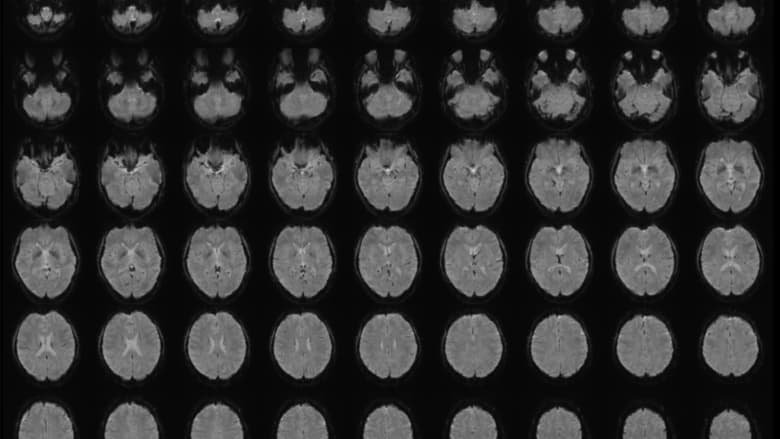

أجرى هوريكاوا تجاربه في مختبرات علوم الاتصال التابعة لشركة NTT في طوكيو، حيث قام بتحليل نشاط الدماغ لدى ستة مشاركين تتراوح أعمارهم بين 22 و37 عامًا، عبر تصوير أدمغتهم أثناء مشاهدتهم 180 مقطع فيديو قصير بلا صوت.

بعدها استخدمت نماذج لغوية ضخمة لإنشاء تعليقات توضيحية تُحوَّل إلى تسلسلات رقمية، ثم درّب الباحث نماذج ذكاء اصطناعي صغيرة تُعرف بـ”Decoders” بهدف مطابقة نشاط الدماغ مع تلك البيانات، وعند اختبار المشاركين على مقاطع جديدة أو أثناء استدعائهم لها من الذاكرة، تمكنت الأدوات الذكية من إنتاج أوصاف نصية متزايدة الدقة للمحتوى المرئي، حتى في الحالات التي لم تُظهر فيها مناطق الدماغ المعنية باللغة نشاطًا ملحوظًا.